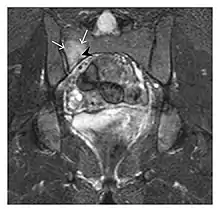

The sacrum is usually masked by overlapping bowel gas in conventional radiographs, and the subtle radiographic findings are usually nondiagnostic and even misleading. The characteristic "H" pattern has been correlated with biomechanical models of patient activities. The vertical parasagittal planes correspond to the region of maximal stress during walking, while the horizontal fracture develops later, secondary to the loss of lateral support by parasagittal fractures. MRI is the primary imaging technique in this case, with the most common MRI pattern showing bone marrow edema and a fracture line (Figure 12). Coronal views are quite contributive in sacral fractures, allowing the detection of the horizontal component, especially with fluid-sensitive sequences. Although the sacrum is the most commonly involved, pelvic insufficiency fractures are often multiple, and other typical locations should be mentioned.[1]

Proximal femoral fractures usually occur in osteoporotic patients, and their signs include subtle neck angulation, trabecular angulation, and subcapital impaction line. A frog-leg lateral view may be helpful if the greater trochanter is short enough. However, positioning can be difficult because of hip pain. In patients with strong suspicion of proximal femoral fracture and negative radiographs, MRI limited to coronal T1 W images and scintigraphy can be highly valuable (Figures 13 and 14). Such an option, with limited examination time, is cost-effective and allows reliable exclusion or confirmation of the diagnosis, preventing an unnecessary stay at the hospital or delayed treatment. Moreover, MRI helps to detect soft tissue abnormalities which are more frequently seen in femoral, acetabular, and pubic injuries than sacral lesions. Concomitant fractures are also frequently seen in typical pelvic sites.[1]

a

b

Figure 13: Partial osseous avulsion of the gluteal muscles at the greater trochanter in a 59-year-old man who presented with the right hip pain without a history of trauma. Lauenstein view and anteroposterior and radiographs (not shown) did not show an obvious fracture line or disruption of bony contours in the acetabulum or the right femoral neck. (a) Coronal T1-weighted MRI displays an incomplete fracture line extending partially from the greater trochanter (arrow). (b) Coronal short tau inversion recovery MRI shows heterogeneous hyperintensity in the same region (arrow) as well as hyperintensity within the gluteus medius and minimus muscles (arrowheads) consistent with tissue edema and hematoma.[1]